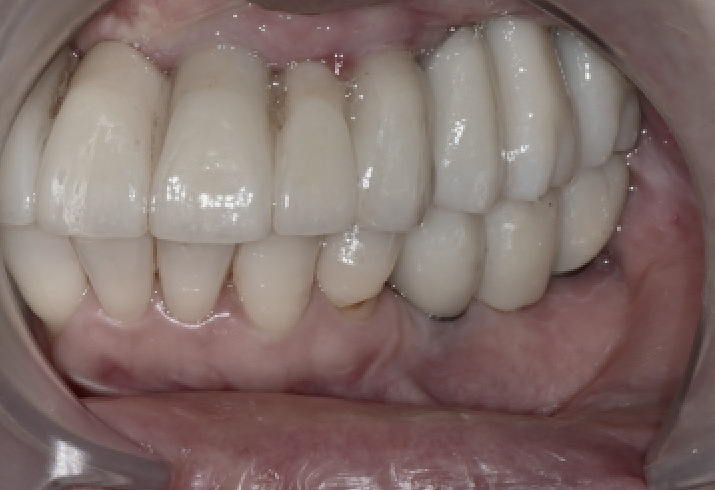

장착 후 3개월 체크

전체임플란트 수술

3개월 뒤 다시 내원하셨을 때

임플란트와 보철물, 잇몸 모두

안정적인 상태였습니다.

왼쪽이 조금 덜 씹힌다는 느낌이 있어

교합면을 아주 미세하게 조정해드렸고,

그 이후에는 편안하게 사용하고 계십니다.